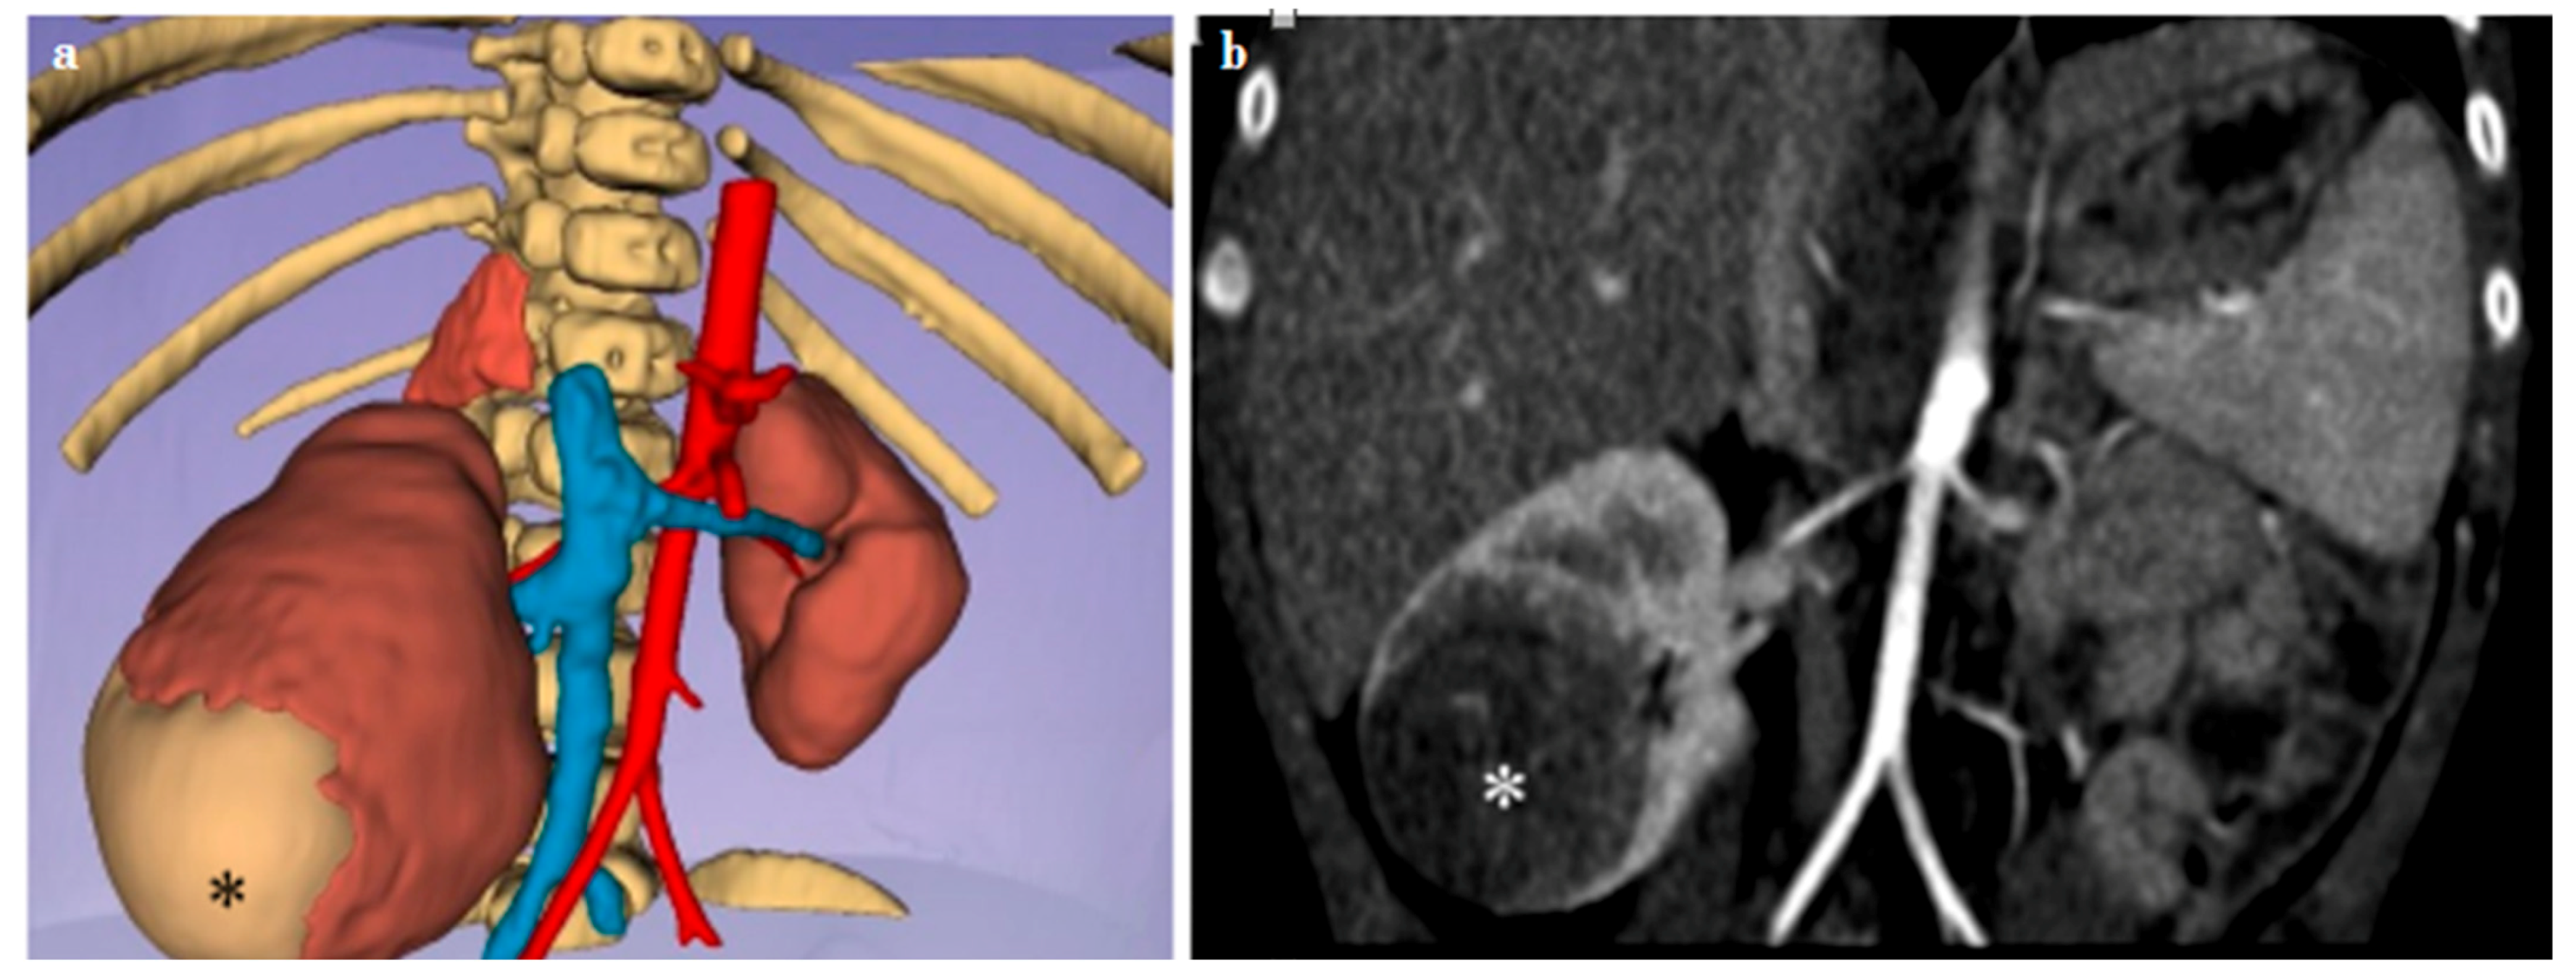

3.3. Kidney Lesions and Congenital Anomalies

| Case n. 6 | Female | 10 years | Ptotic and hypodysplastic kidney | Right |